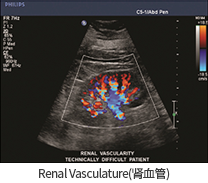

• Renal Vasculature (신장혈류)